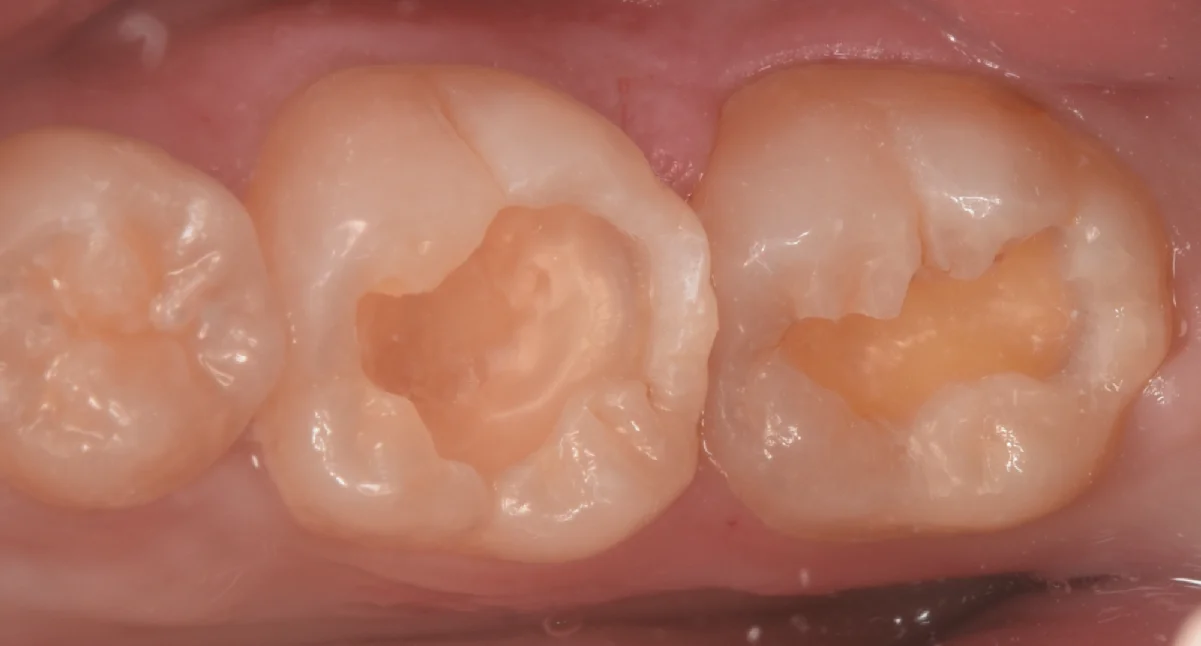

虫歯を取り切ったのがこちらになります。

本来の歯の色がしっかりと出ています。

真ん中の歯は虫歯が大きすぎて、表層のエナメル質しか残っていない状況で、内部の象牙質の大部分はすでに虫歯で失われている状態でした。